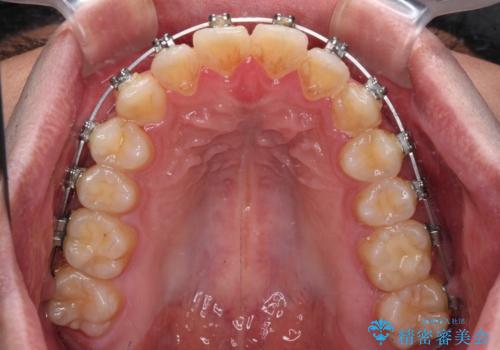

- 矯正装置

- メタルブラケット

- 前歯のデコボコを治したいとのことで来院された患者様です。

できる限り楽して、短期間で治したいとのことで、ワイヤー装置にて矯正治療を行うこととしました。